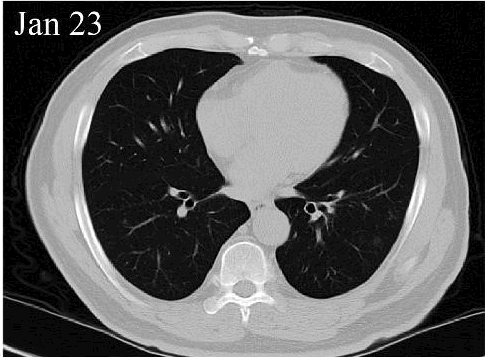

患肺炎后,胸部CT可表现为多种形式,通常会有斑片状、磨玻璃、网格状等阴影,需要医生根据具体影像判断。

感染新冠后,病毒细菌等病原体仅累及上呼吸道时,通常会出现咳嗽,CT检查没有肺炎症状;当炎症累及下呼吸道,就可能发展成肺炎。

CT/X光检查 | 肺纹理清晰 | 有阴影 |